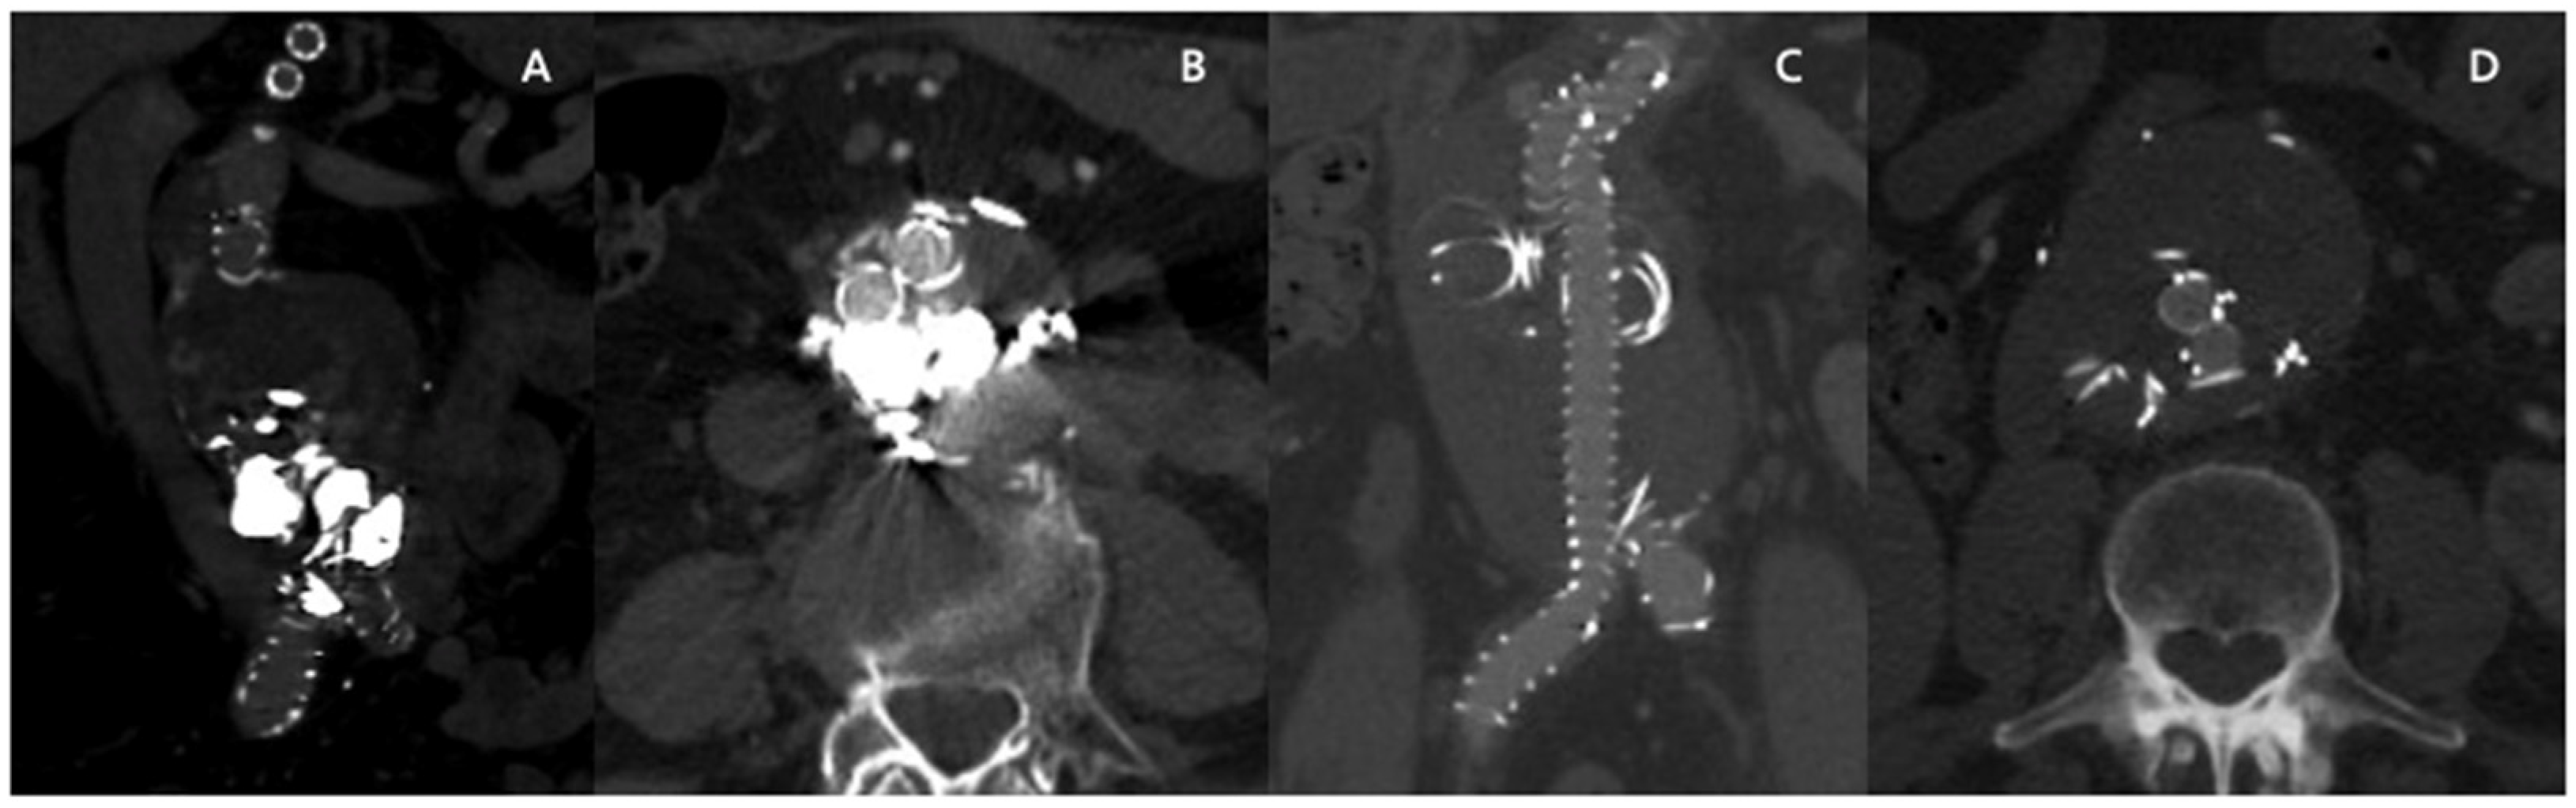

Embo F/BEVAR Case Descriptions and Preliminary Results